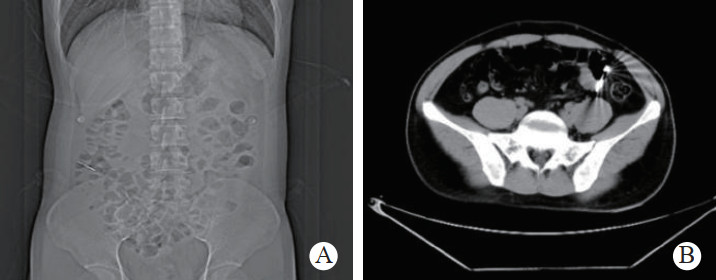

1 一般资料患者,男性,32岁,职员,因“误吞金属钉状物7 d”就诊。患者7 d前误吞入金属钉状物一根(大小约3 cm),患者无明显不适症状,未诊治。4 d前出现下腹隐痛,行急诊全腹CT检查,见图 1,行急诊胃镜检查未见明显异物。后复查腹部CT示异物进入小肠内(图 2),普外科会诊建议随访。2 d前复查腹部CT(图 3),继续保守治疗。1 d前患者为行异物取出入院,复查腹部CT可见异物至结肠内(图 4)。急诊予以聚乙二醇电解质散导泻清肠,行无痛肠镜下异物取出术。本文已通过本院伦理委员会审批,伦理审批号为:(2021)伦审研第(0252)号,并通过免除知情同意申请。完善术前检查,进行药物导泻清肠时,关注患者有无腹痛等现象,以免因服用药物清肠,肠蠕动加快,尖锐异物在消化道内随蠕动前行,尖端嵌插在肠壁中而停滞不前,并随着后方内容物的推进,加深尖锐异物刺入肠壁,最终导致穿孔及出血的发生。本例患者安置在独立单人间进行肠道准备,不定时进行腹部查体及观察排泄物的性状,早期发现穿孔、出血指征,以便尽早进行外科手术干预。与此同时,内镜中心医护人员联合外科、放射科、麻醉科医生制定诊疗方案,若发生此类情况,立即予急诊行腹部X线或CT检查,一旦确定出现穿孔或出血等情况,即刻行急诊手术治疗。

| 图 1 腹部CT示胃窦幽门部尖锐异物 |